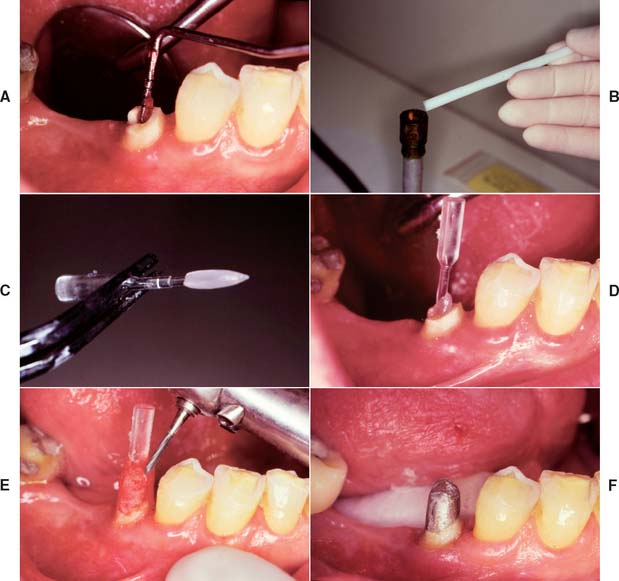

There are two commonly used methods to remove gutta-percha (Fig. 12-23): (1) using a warmed endodontic plugger, and (2) using a rotary instrument, sometimes in conjunction with chemical agents. Although more time consuming, the warmed endodontic plugger is preferred because it eliminates the possibility that the rotary instrument will inadvertently damage the dentin. If it is more convenient, the gutta-percha can be removed with a warmed condenser immediately after obturation. This does not disturb the apical seal.55,56 This method offers the additional advantage of allowing the operator to work in an area where the root canal anatomy is still familiar.

Fig. 12-23 Gutta-percha can be removed from the canal with a heated endodontic plugger. (A and B), a non–end-cutting bur (C) (e.g., a Gates Glidden drill). A ParaPost drill (D) can be used to parallel the post space wall (with a rubber stop to ensure accuracy of the preparation depth).

(A and B, Courtesy of Dr. D. A. Miller.)

After the post space has been prepared, the remaining coronal tooth structure is reduced for the extracoronal restoration. Specific reduction depends on the type of crown that is planned. When esthetic requirements apply, as for anterior teeth, metal-ceramic crowns or all-ceramic crowns are indicated. (see Chapters 9, 11, 24, and 25).